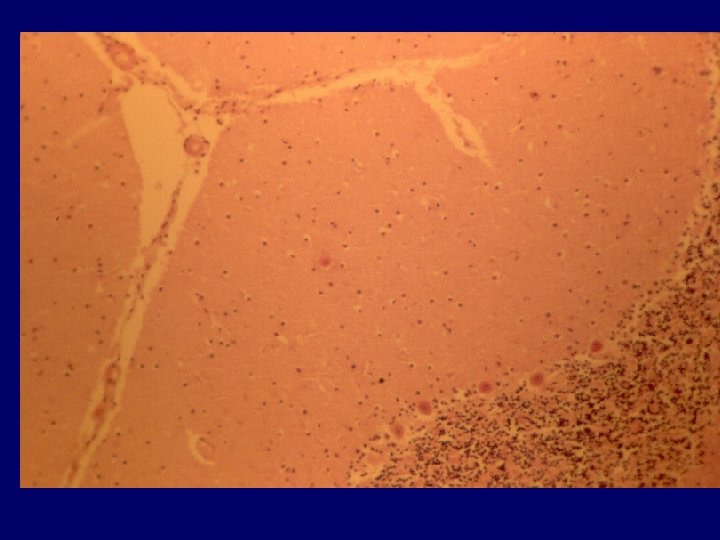

PREPARAÇÃO DO MATERIAL (TÉCNICA) Usar luvas. Cortar o cérebro sobre toalha plástica não permeável, que deve ser incinerada após. Mergulhar os fragmentos em ácido fórmico a 95% ou 100% por uma hora seguido de formol a 4% por 24 horas. Todos os instrumentos devem ser descontaminados.